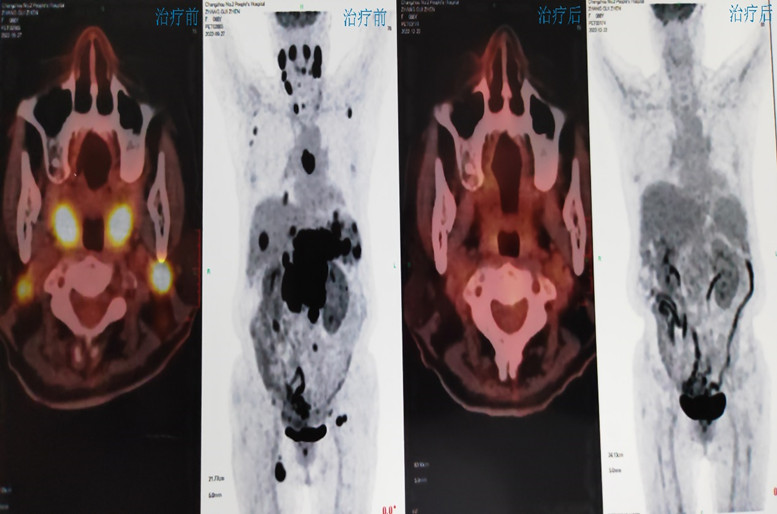

淋巴瘤团队:由贾祝霞博士领衔,陈涛科副主任、主任医师担任临床技术指导。开展MDT模式的全流程淋巴瘤诊疗,联合影像科、病理科等科室建立淋巴瘤快速精确诊断绿色通道;开展基于二代测序(NGS)检测的精准分层治疗,针对不同患者,选择化疗、靶向治疗、免疫治疗等个体化治疗手段;实现CART治疗全流程管理,从淋巴细胞采集、体外扩增到回输后CRS等不良反应管理,建立标准化操作流程;开展干细胞移植桥接CART治疗,为高危预后不佳的淋巴瘤患者提供根治性治疗方案;同时牵头和参与多项前沿性临床研究,为患者提供更多的治疗选择。2024年初,淋巴瘤团队率先创新性应用双抗(Glofitamab)治疗一例复发难治原发中枢神经系统淋巴瘤,患者达到完全缓解。总之,淋巴瘤团队以“精准、温度、创新”为核心理念,致力于打造一流的淋巴瘤诊疗中心,为患者提供“一站式”全周期解决方案。